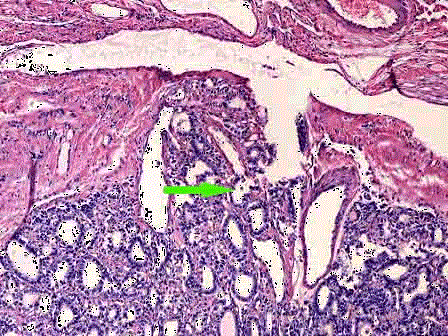

问题 图1为胃中低分化腺癌镜下观,图2为甲状腺滤泡癌镜下观,箭头所指表示了肿瘤的哪几种侵犯方式 ( )

选项 A.侵犯包膜 B.侵犯神经 C.侵犯脉管 D.侵犯表皮 E.以上都不是

答案 ABC